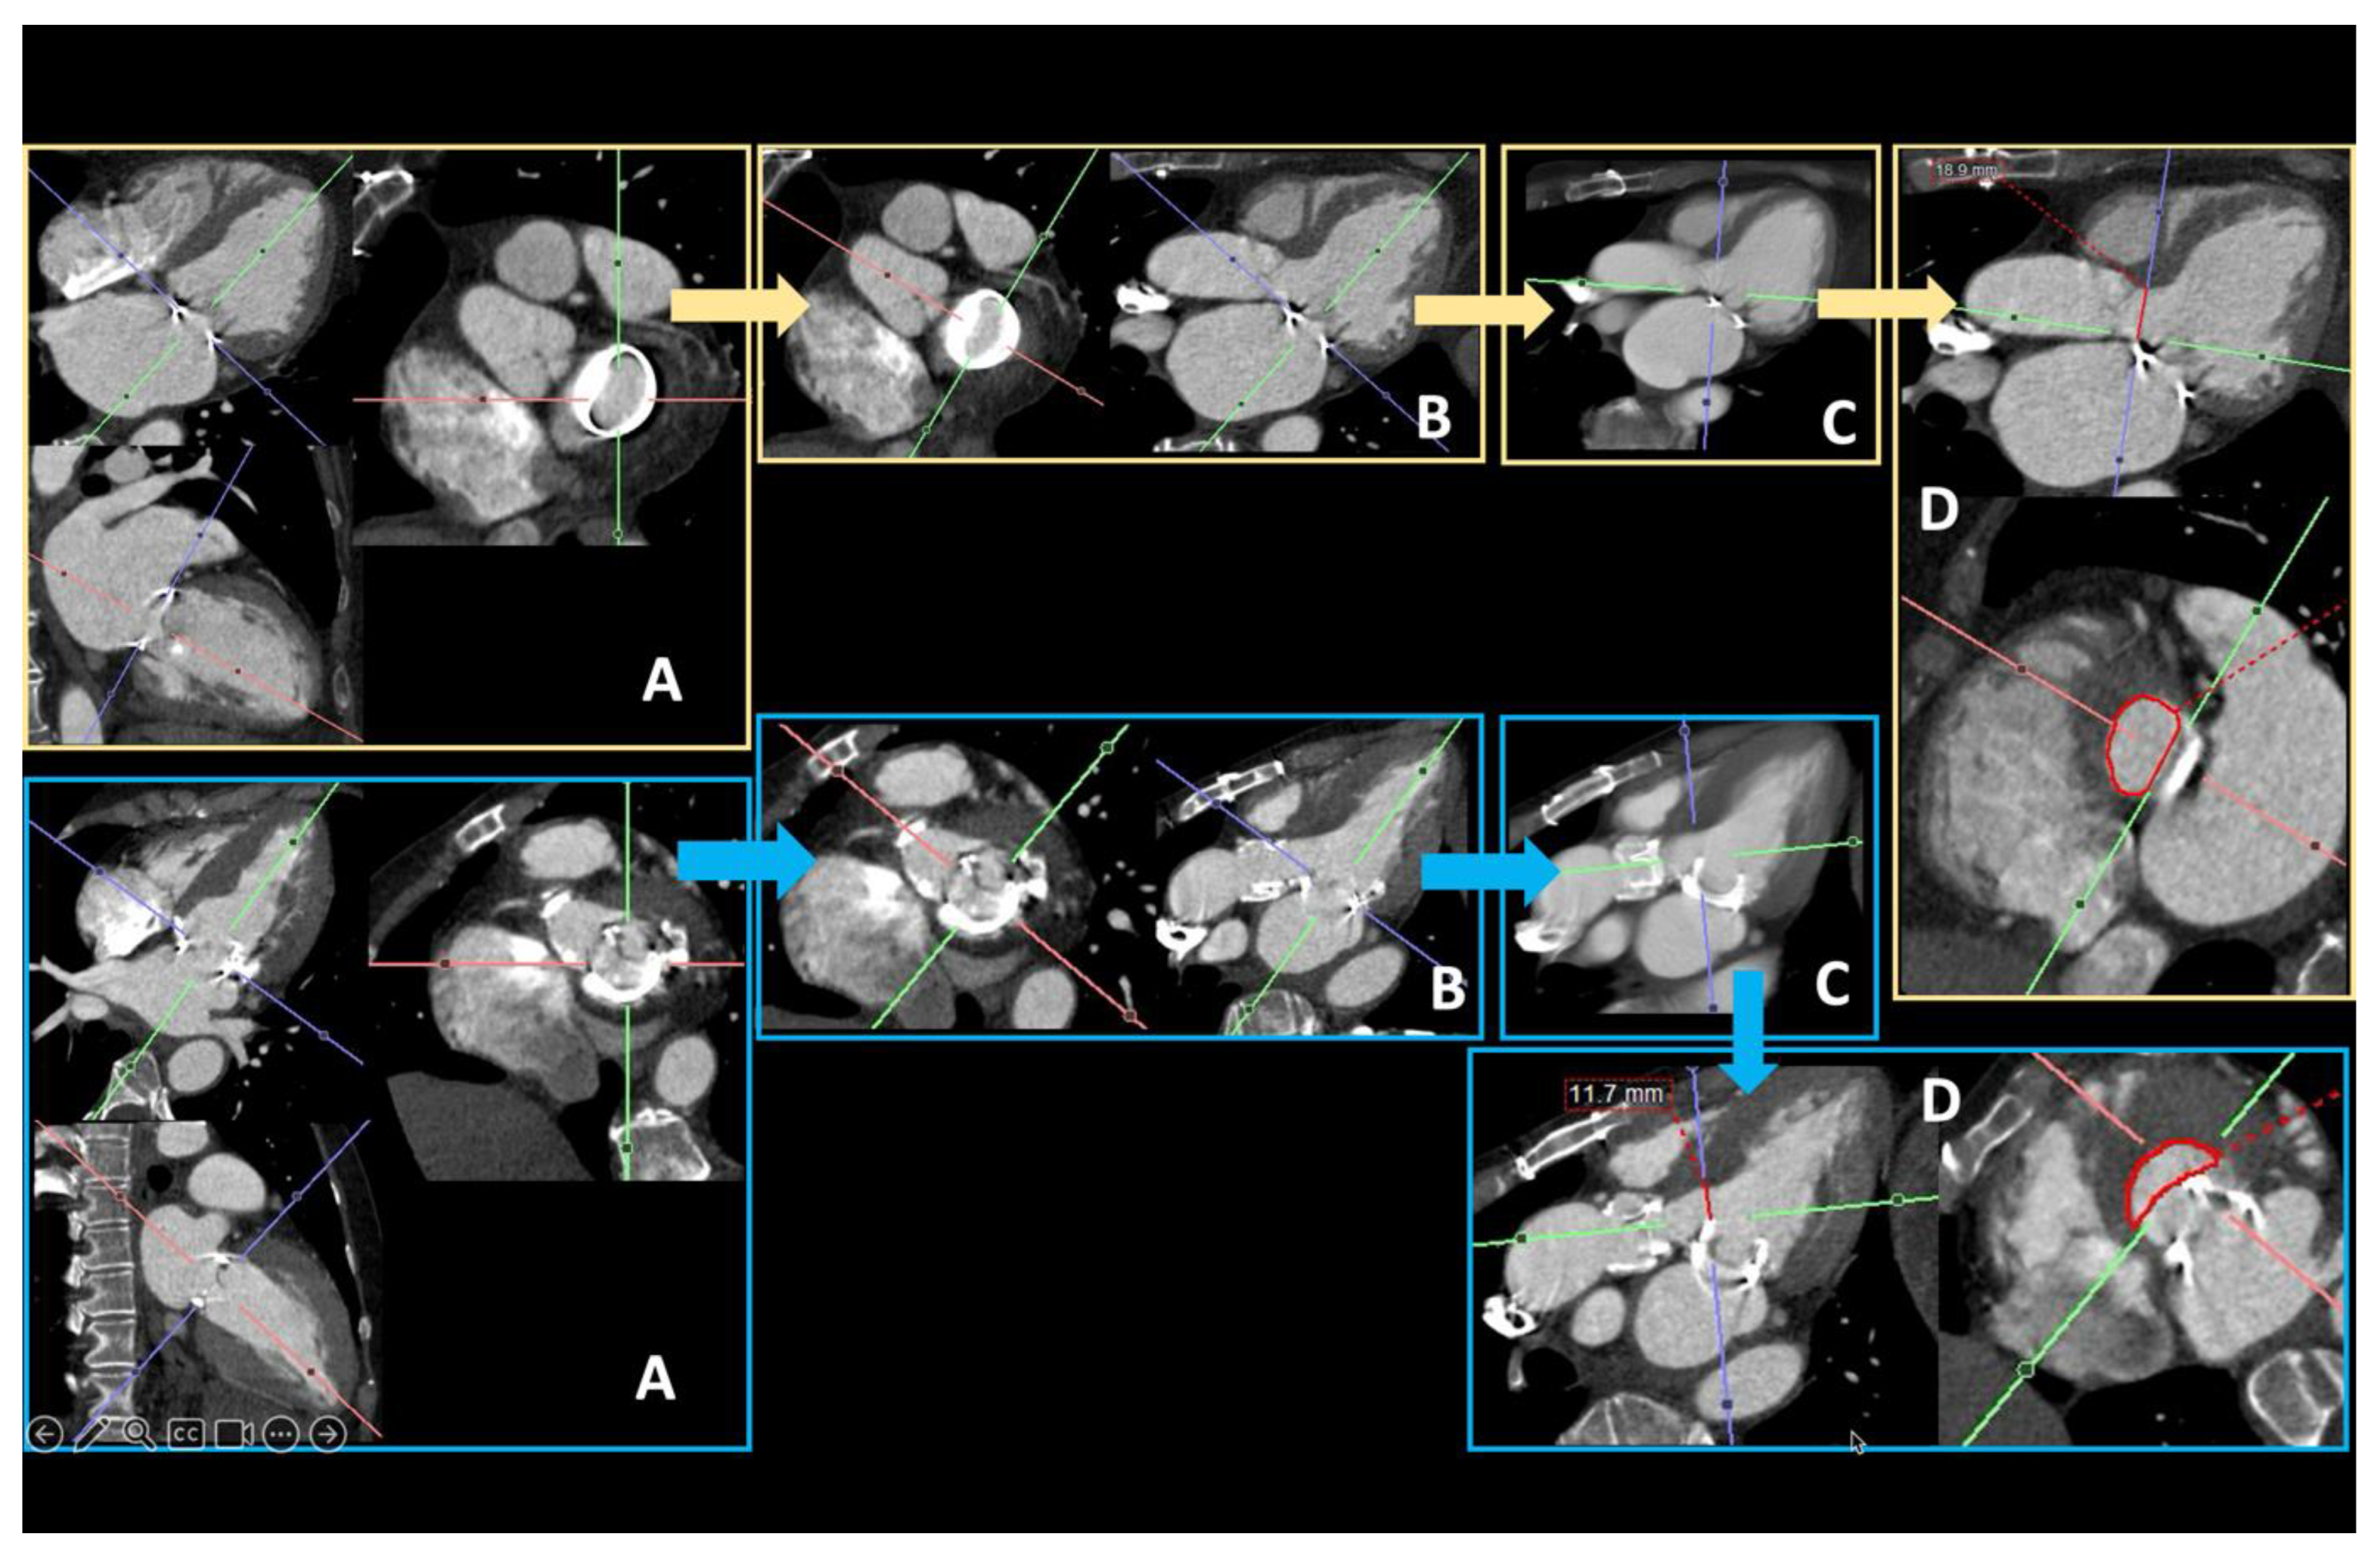

- Hell, M.M.; Emrich, T.; Kreidel, F.; Kreitner, K.-F.; Schoepf, U.J.; Münzel, T.; von Bardeleben, R.S. Computed tomography imaging needs for novel transcatheter tricuspid valve repair and replacement therapies. Eur. Heart J. Cardiovasc. Imaging 2020, 22, 601–610. [Google Scholar] [CrossRef] [PubMed]

- van Rosendael, P.J.; Kamperidis, V.; Kong, W.K.; van Rosendael, A.R.; van der Kley, F.; Ajmone Marsan, N.; Delgado, V.; Bax, J.J. Computed tomography for planning transcatheter tricuspid valve therapy. Eur. Heart J. 2017, 38, 665–674. [Google Scholar] [CrossRef] [PubMed]

- Naoum, C.; Blanke, P.; Cavalcante, J.L.; Leipsic, J. Cardiac Computed Tomography and Magnetic Resonance Imaging in the Evaluation of Mitral and Tricuspid Valve Disease. Circ. Cardiovasc. Imaging 2017, 10, e005331. [Google Scholar] [CrossRef]